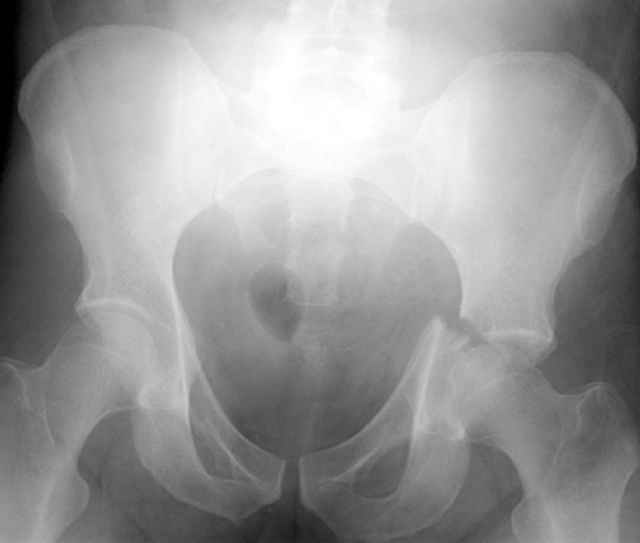

Prone Obturator-Outlet

Screw insertion using the obturator-outlet combination image.

12.Prone Obturator-Outlet

Same with a contoured pelvic reconstruction plate applied and tensioned.